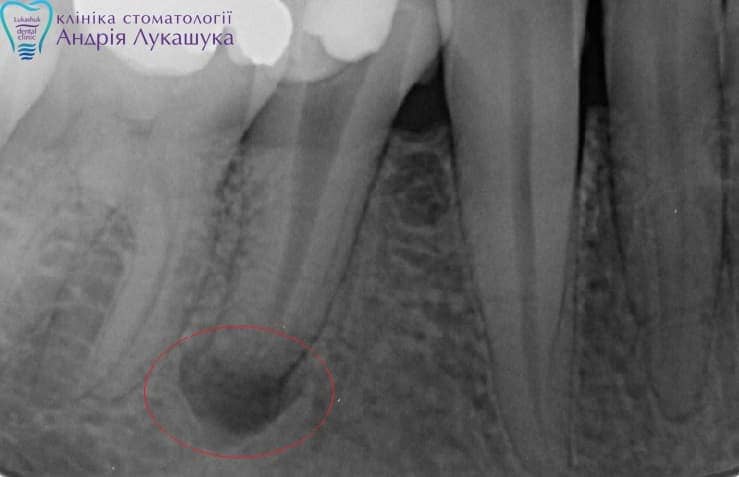

При длительном течении процесса околоверхушечная костная ткань постепенно разрушается, образующийся дефект замещается грануляционной тканью.

В одних случаях у больного вокруг грануляционной ткани образуется плотная фиброзная капсула — зубная гранулема, которая со временем может превратиться в кисту, заполненную гноем и продуктами воспаления.

Основными симптомами периодонтита в острой стадии является резкая, локализованная боль в области конкретного зуба, усиливающаяся от горячего и от накусывания на него, синдром «увеличившегося зуба» и его подвижность, неприятный запах изо рта и отечность десны с возможным образованием свищей. При хроническом периодонтите боль и другие симптомы не настолько выражены или отсутствуют совсем, и диагностируются только при стоматологическом и рентгенологическом обследовании.

- Фиброзная форма хронического периодонтита является начальной и практически незаметна — боли носят несистематический характер, или полностью отсутствуют, и определить наличие воспалительного процесса можно только при помощи рентгеновского снимка.

- Гранулирующая самая распространенная форма в стоматологической практике. Ее протекание сопряжено с постоянными болями, сильными отеками и выделением гноя из десны.

- Гранулематозная — серьезней всех остальных. При эволюции заболевания до этой стадии в мягких тканях образуются гранулемы — дёсенные пустоты, которые заполнены гноем, представляющим собой идеальную среду для жизни микробов. Они фактически представляют собой мину замедленного действия, и удаляются только хирургическим путем.